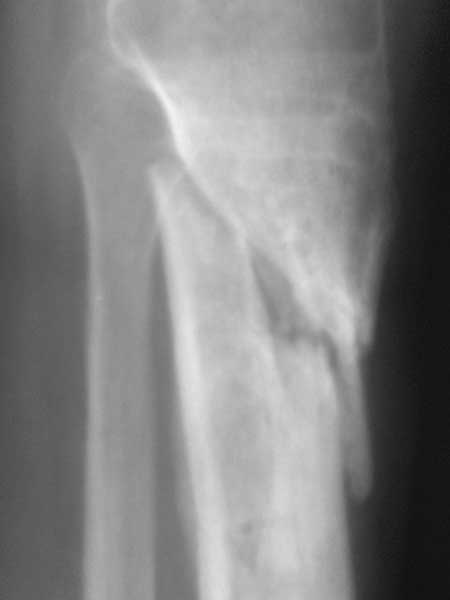

Жаль, что нет фасной проекции. Перелом на 2 уровнях, есть искривление костно-мозгового канала. Проксимальный отломок короткий. Вывод: лучше не штифтовать.

Спасибо за обсуждение.Отправил остальные R, изиняюсь за качество.

3.Перелом на 2 уровнях, есть искривление костно-мозгового канала. Проксимальный отломок короткий.

Ни одного снимка, где было бы видно коленный сустав.. Не совсем понимаю столь яростное отрицание стержня, проксимальный отломок не так уж и короток, 3 разнонаправленных винта войти смогут. Учитывая продление на диафиз, если выбирать между здоровенной пластиной и стержнем, ИМХО целесообразнее стержень.

Все таки решились на штифт с антибиотическим покрытием. Выставляю R, в целом считаю неплохо вроде получилось.